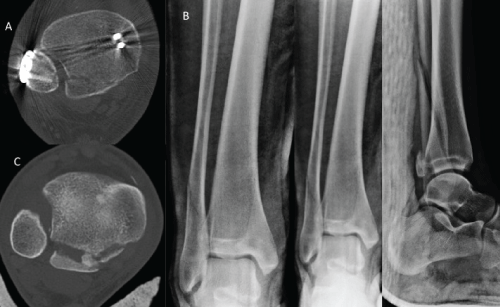

A 15-year-old female was present in our clinic 2 days after sustaining an injury to her right ankle during a 400 meters hurdle competition. On physical examination, mild swelling and localized tenderness at the anterior lateral aspect of her ankle was revealed. Plain radiographs were suspicious for a Tillaux fracture (Figure 2). A CT scan of her ankle revealed an isolated Tillaux fragment that is located at anterolateral aspect of distal tibial articular surface with syndesmosis diastasis (Figure 3).

Figure 2: Plain radiographs of anteroposterior (AP), mortise, and lateral views. AP view was showing that anterolateral intra-articular fracture of epiphysis. However, mortise and lateral views did not reveal any abnormalities.

Figure 3: CT scans of the injured ankle. Anterolateral Tillaux fragment was displaced laterally on coronal reconstruction image and was displaced anteriorly on sagittal reconstruction image. Axial image showed that anterolateral fragment without posterior extension, but displaced anteriorly and laterally with fibula shifting anteriorly.